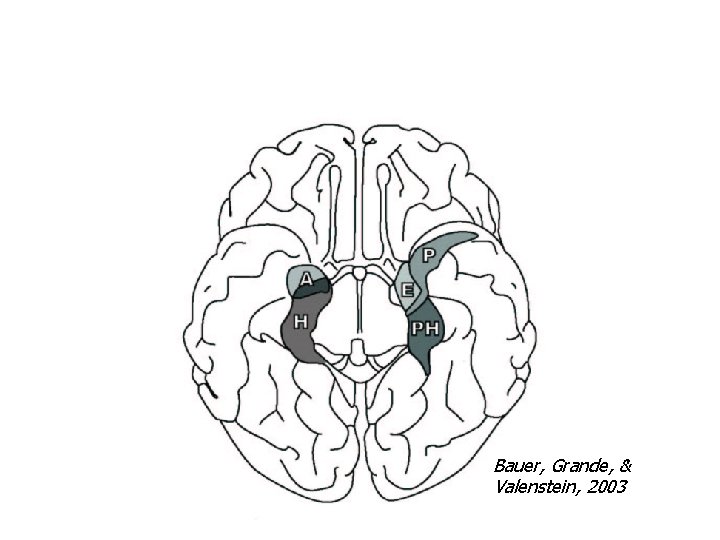

Bauer, Grande, & Valenstein, 2003

Integrated Circuitry Linking Temporal, Diencephalic, and Basal Forebrain Regions